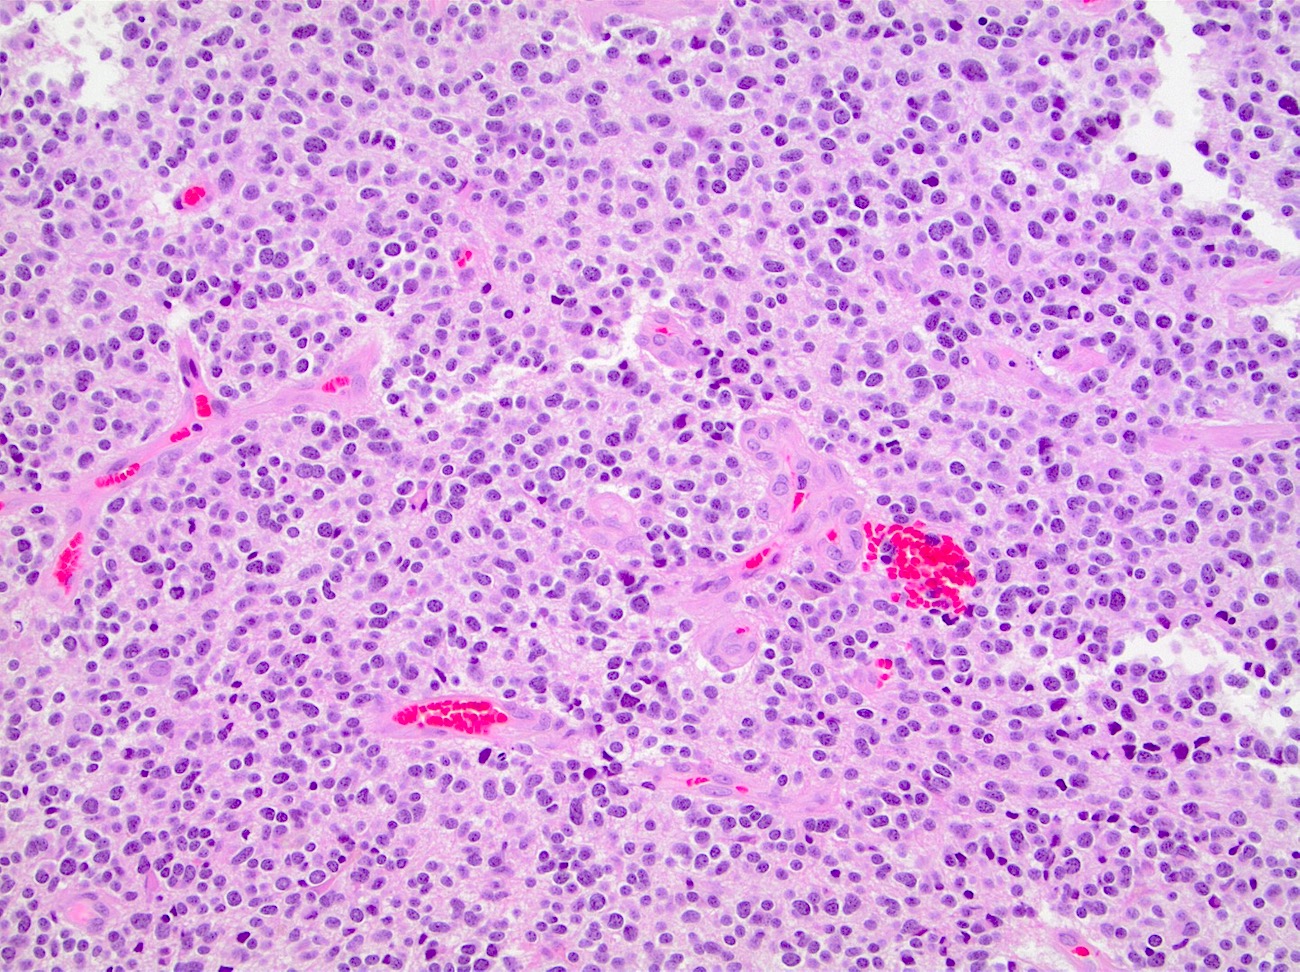

Microscopic (histologic) description

- Closely packed cells with small, round, monotonous nuclei (slightly larger than a normal oligodendrocyte)

- Perinuclear clearing (fried egg appearance)

- Formalin fixation artifact

- Will not be seen on frozen sections or smear preparations

- Network of thin walled, branching blood vessels (chicken wire vasculature)

- Microcalcifications (calcospherites) are characteristic

- Presence of perineural, perivascular or subpial aggregates of tumor cells (secondary structures of Scherer)

- Occasional mitoses and moderate nuclear atypia are still consistent with grade 2 designation (J Neuropathol Exp Neurol 2001;60:248)

- Not uncommon to find well differentiated / fibrillary astrocytic morphology (Acta Neuropathol 1984;64:265)

Microscopic (histologic) images

Contributed by Jared T. Ahrendsen, M.D., Ph.D. and John DeWitt, M.D., Ph.D.